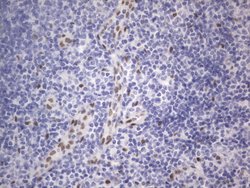

RBFOX1 Mouse anti-Human, Clone: OTI4F9, lyophilized, TrueMAB™

| Immunohistochemistry (Paraffin), Western Blot | |